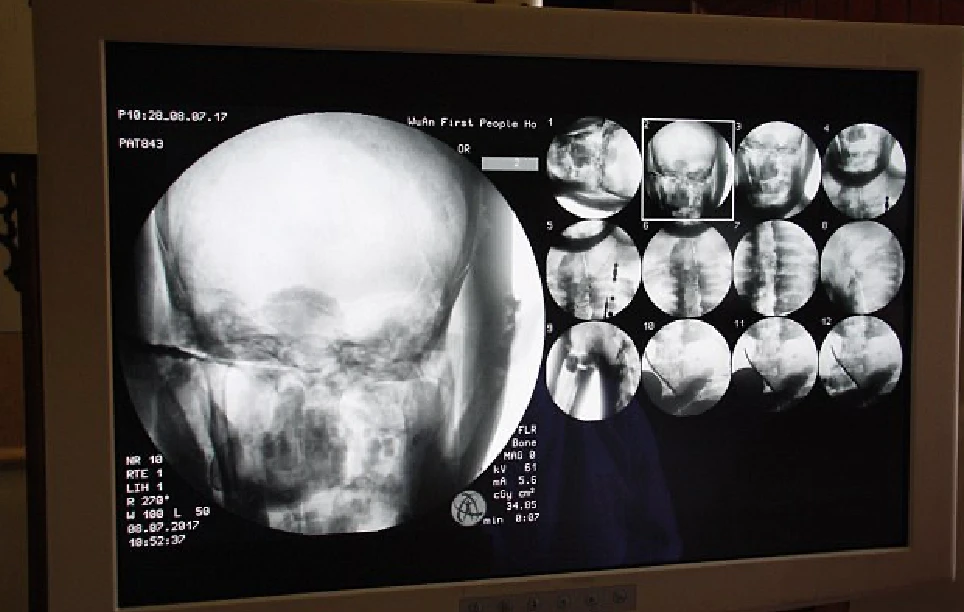

Bước ngoặt thực sự diễn ra vào ngày 8 tháng 7 năm 2017, khi các nhà khoa học phối hợp cùng bệnh viện địa phương quyết định tiến hành chụp CT (cắt lớp vi tính) ngay tại khuôn viên nhà chùa dưới sự chứng kiến của giới truyền thông và hàng nghìn người dân hiếu kỳ. Khi những hình ảnh quét đầu tiên xuất hiện trên màn hình máy tính, cả khán phòng đã rơi vào trạng thái im lặng đến nghẹt thở vì kinh ngạc.

Dưới lớp mạ vàng dày, hình ảnh quét CT hiện rõ mồn một cấu trúc của một cơ thể người hoàn chỉnh. Bác sĩ Wu Yongqing, người trực tiếp điều hành buổi kiểm tra, đã phải thốt lên rằng đây là một kỳ tích chưa từng thấy trong y học và khảo cổ. Kết quả cho thấy toàn bộ hệ thống xương của nhà sư Ci Xian vẫn chắc khỏe và rõ nét như của một người đang sống.

Từ những chi tiết nhỏ nhất như xương hàm trên, hàm răng đều tăm tắp cho đến xương sườn, xương sống và các khớp xương đều giữ được vị trí nguyên vẹn, không hề có dấu hiệu của sự phân hủy hay mục nát do thời gian. Đáng kinh ngạc hơn cả chính là bộ não của ngài; thay vì bị teo hoàn toàn theo quy luật tự nhiên, hình ảnh quét cho thấy khối óc vẫn còn giữ được hình dáng cấu trúc tương đối hoàn chỉnh, nằm bình yên bên trong hộp sọ.